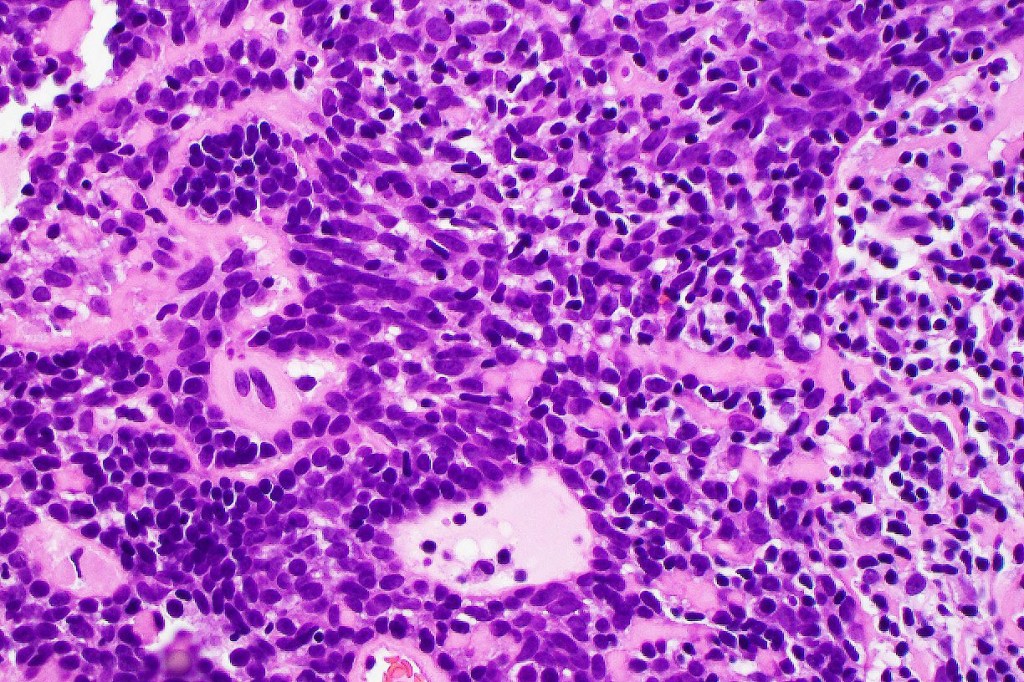

•Outer layer of small intensely basophilic cells surrounding larger pale staining or eosinophilic cells with vesicular nuclei & small nucleoli

•Intra-tumoral lymphocytes

•No pleomorphism & only sparse mitoses or no mitoses

•Basement membrane thickening & intralobular eosinophilic globules